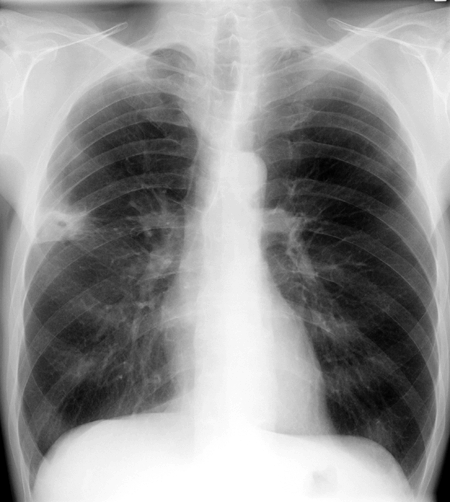

Beurteilung der Lungenfelder

Normalbefund